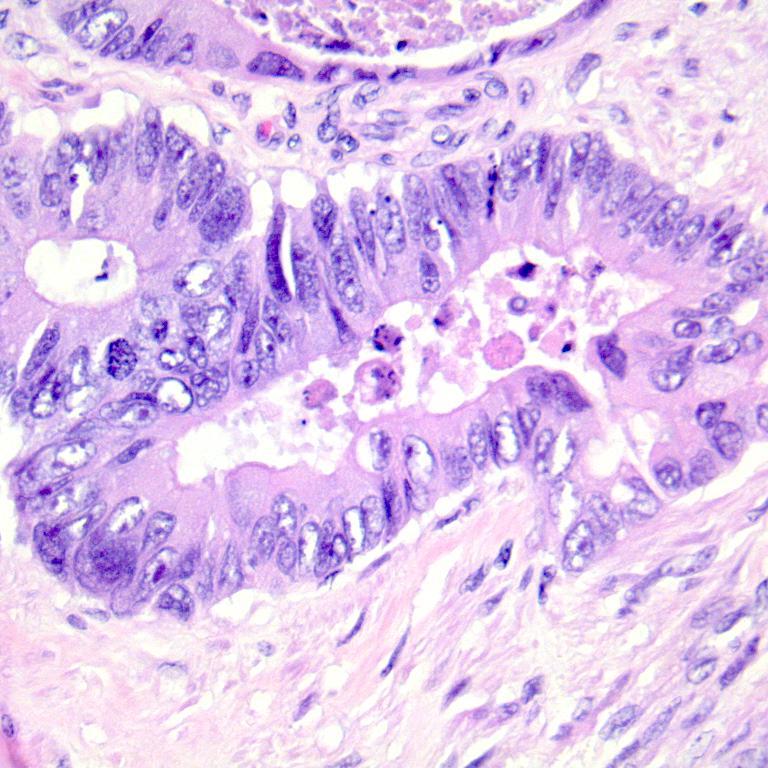

We consider two binary histopathology classification tasks, both framed as “cancer” vs. “non cancer”. The first dataset is the Ovarian Cancer & Subtypes Histopathology dataset111https://www.kaggle.com/datasets/bitsnpieces/ovarian-cancer-and-subtypes-dataset-histopathology, which contains digital pathology patches extracted from hematoxylin and eosin (H&E) stained ovarian tissue slides. We group the available subtypes into a single positive class (ovarian cancer) and use benign or non tumoral tissue as the negative class.

The second dataset is a subset of the LC25000 dataset222https://www.kaggle.com/andrewmvd/lung-and-colon-cancer-histopathological-images, which contains colon histopathology images with normal and tumoral samples. We select only colon images and map them to a binary label (cancer vs. non cancer). Representative examples of ovarian and colon patches for both classes (Figure 2).

| (a) Ovarian cancer | ||

| (b) Ovarian normal | ||

| (c) Colon cancer | ||

| (d) Colon normal | ||